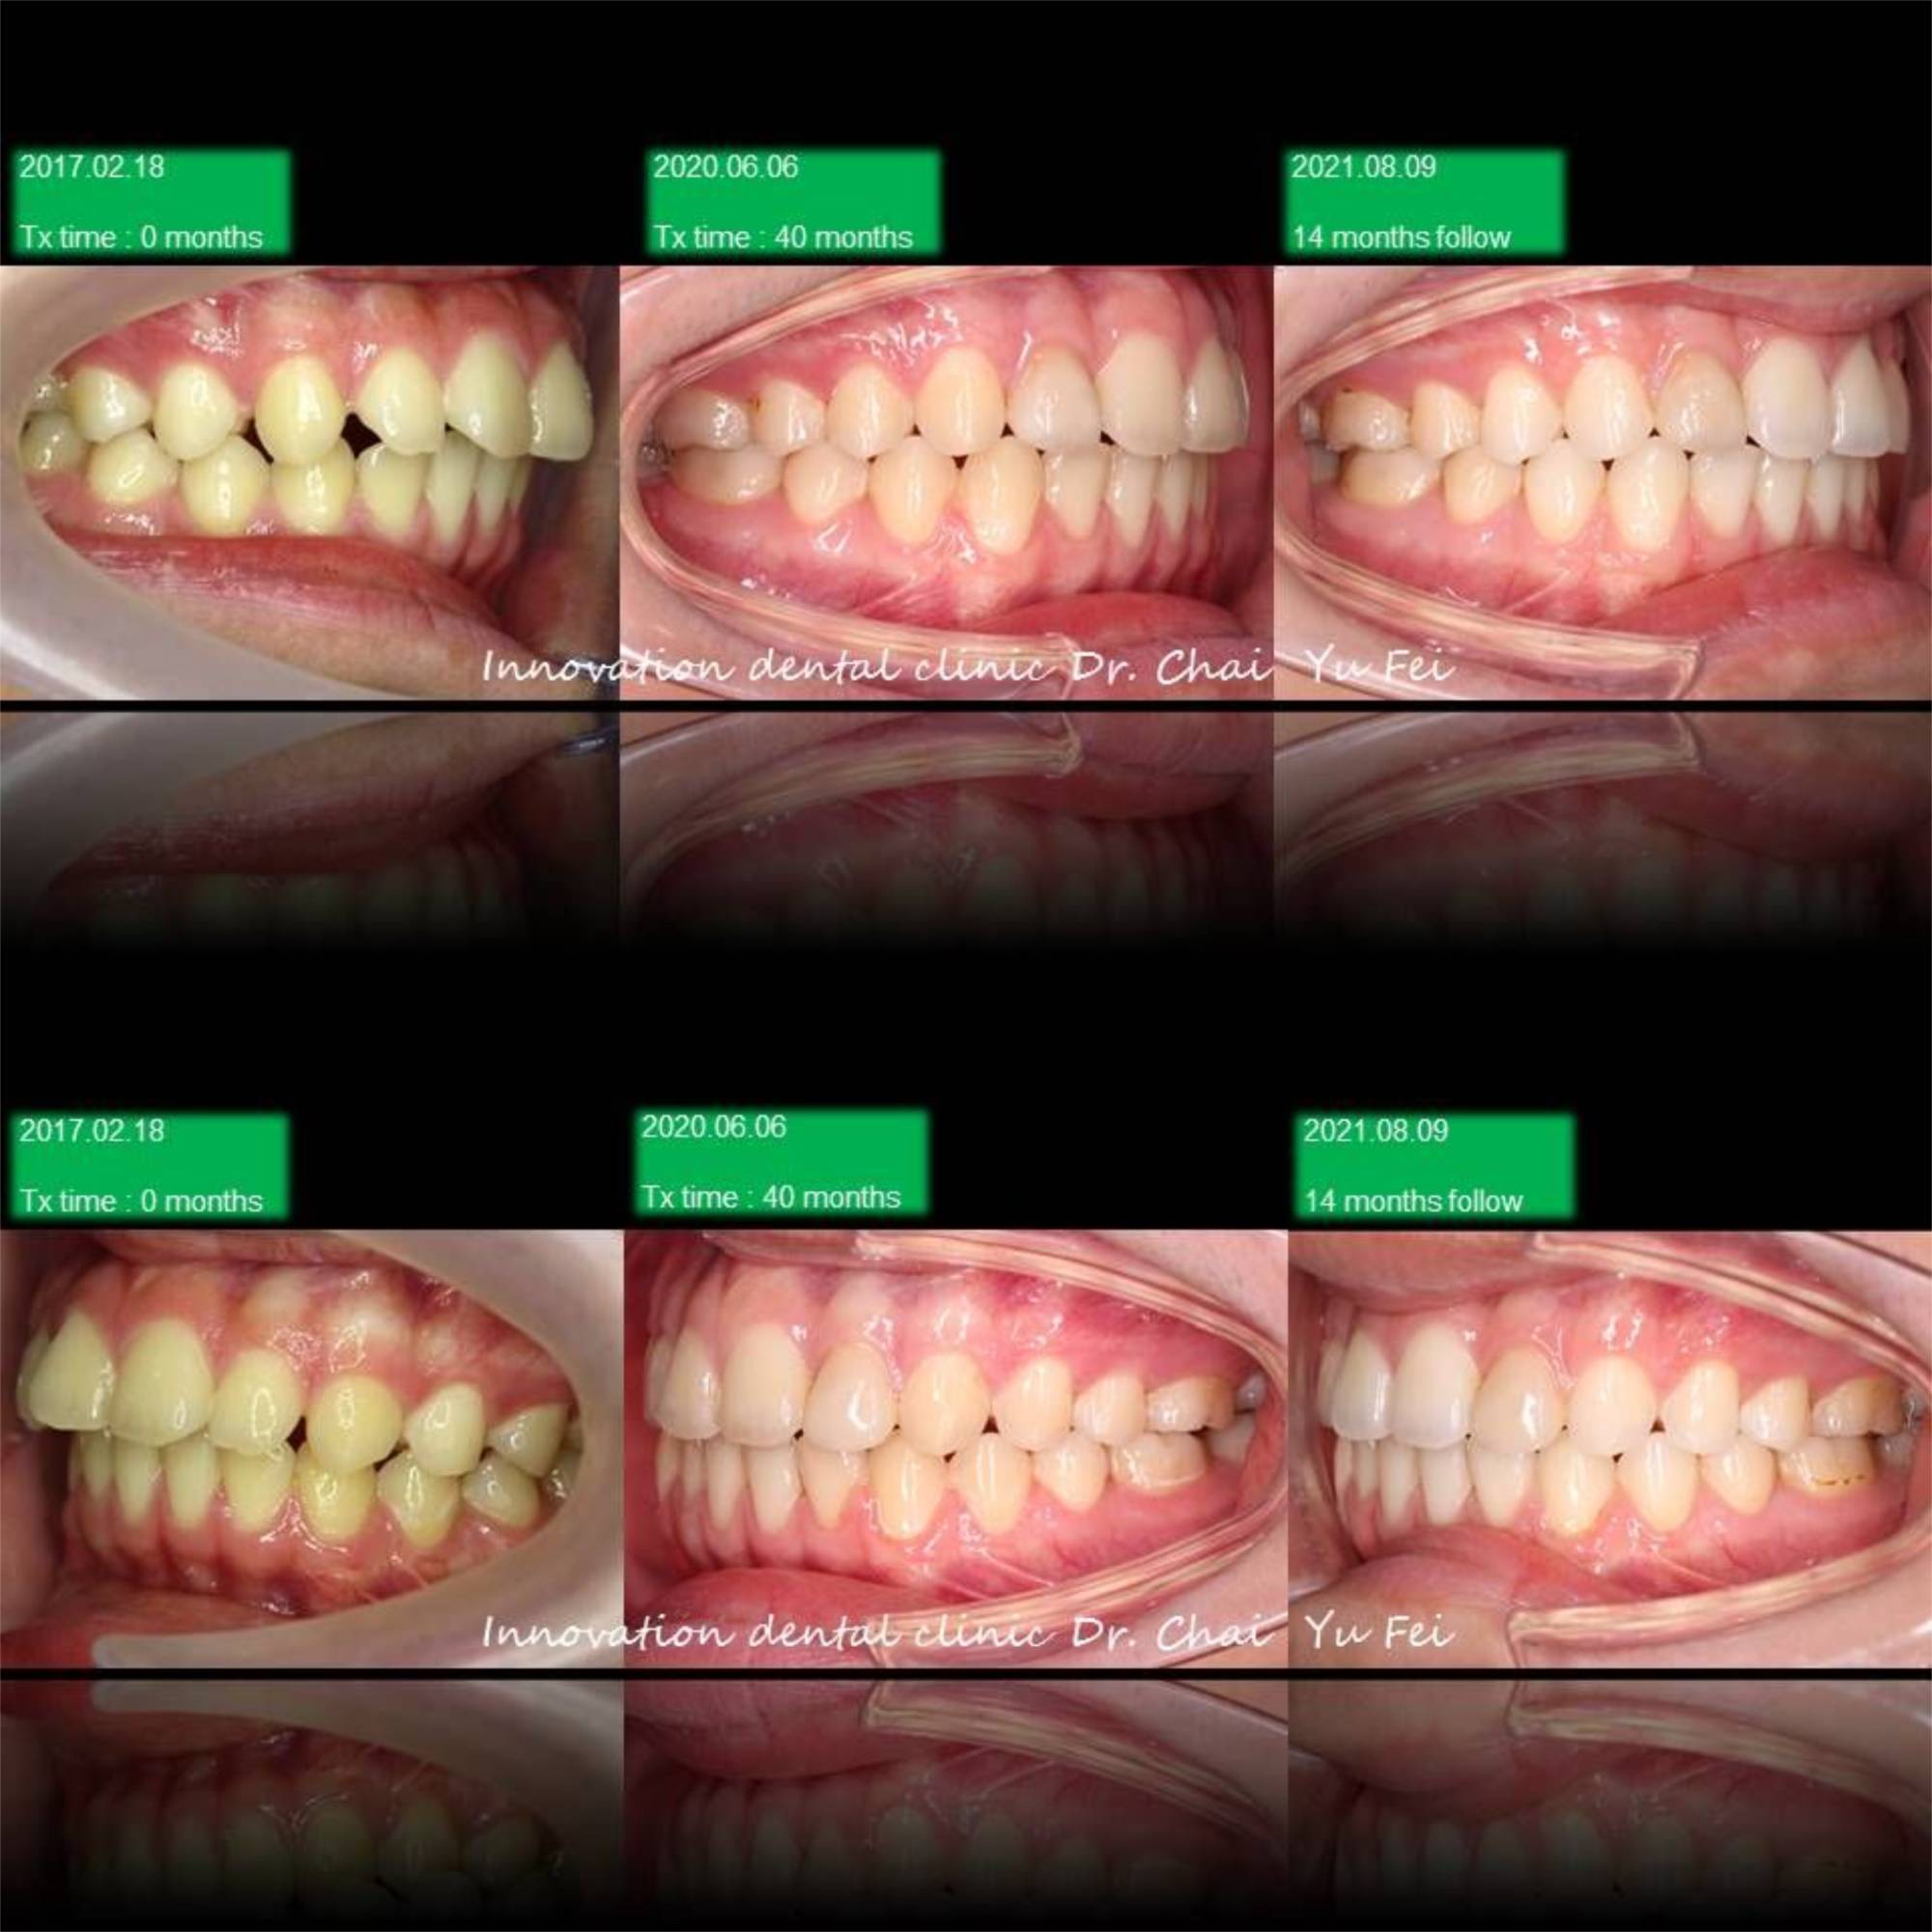

[ 治療方式 ] : 利用矯正 , 將前突的齒列內收,改善外觀,右側咬合高度喪失重建,植牙,恢復美觀功能

[ 治療時間 ] : 40 個月

男生的發育都是很長遠的,看到初始這樣的暴牙可能會擔心需要拔牙改善,但是考量孩子的年紀與生長潛力

我們採用上顎到後期用骨釘加一層保險去控制,下顎讓孩子自然生長的方式,現在這位高材生都已經升大學了

Non-extraction case .

Upper control by mini screw , lower let him grow automatically

很感謝他矯正期間的配合,很有耐心地讓我在最後改中線的部分花了不少時間。